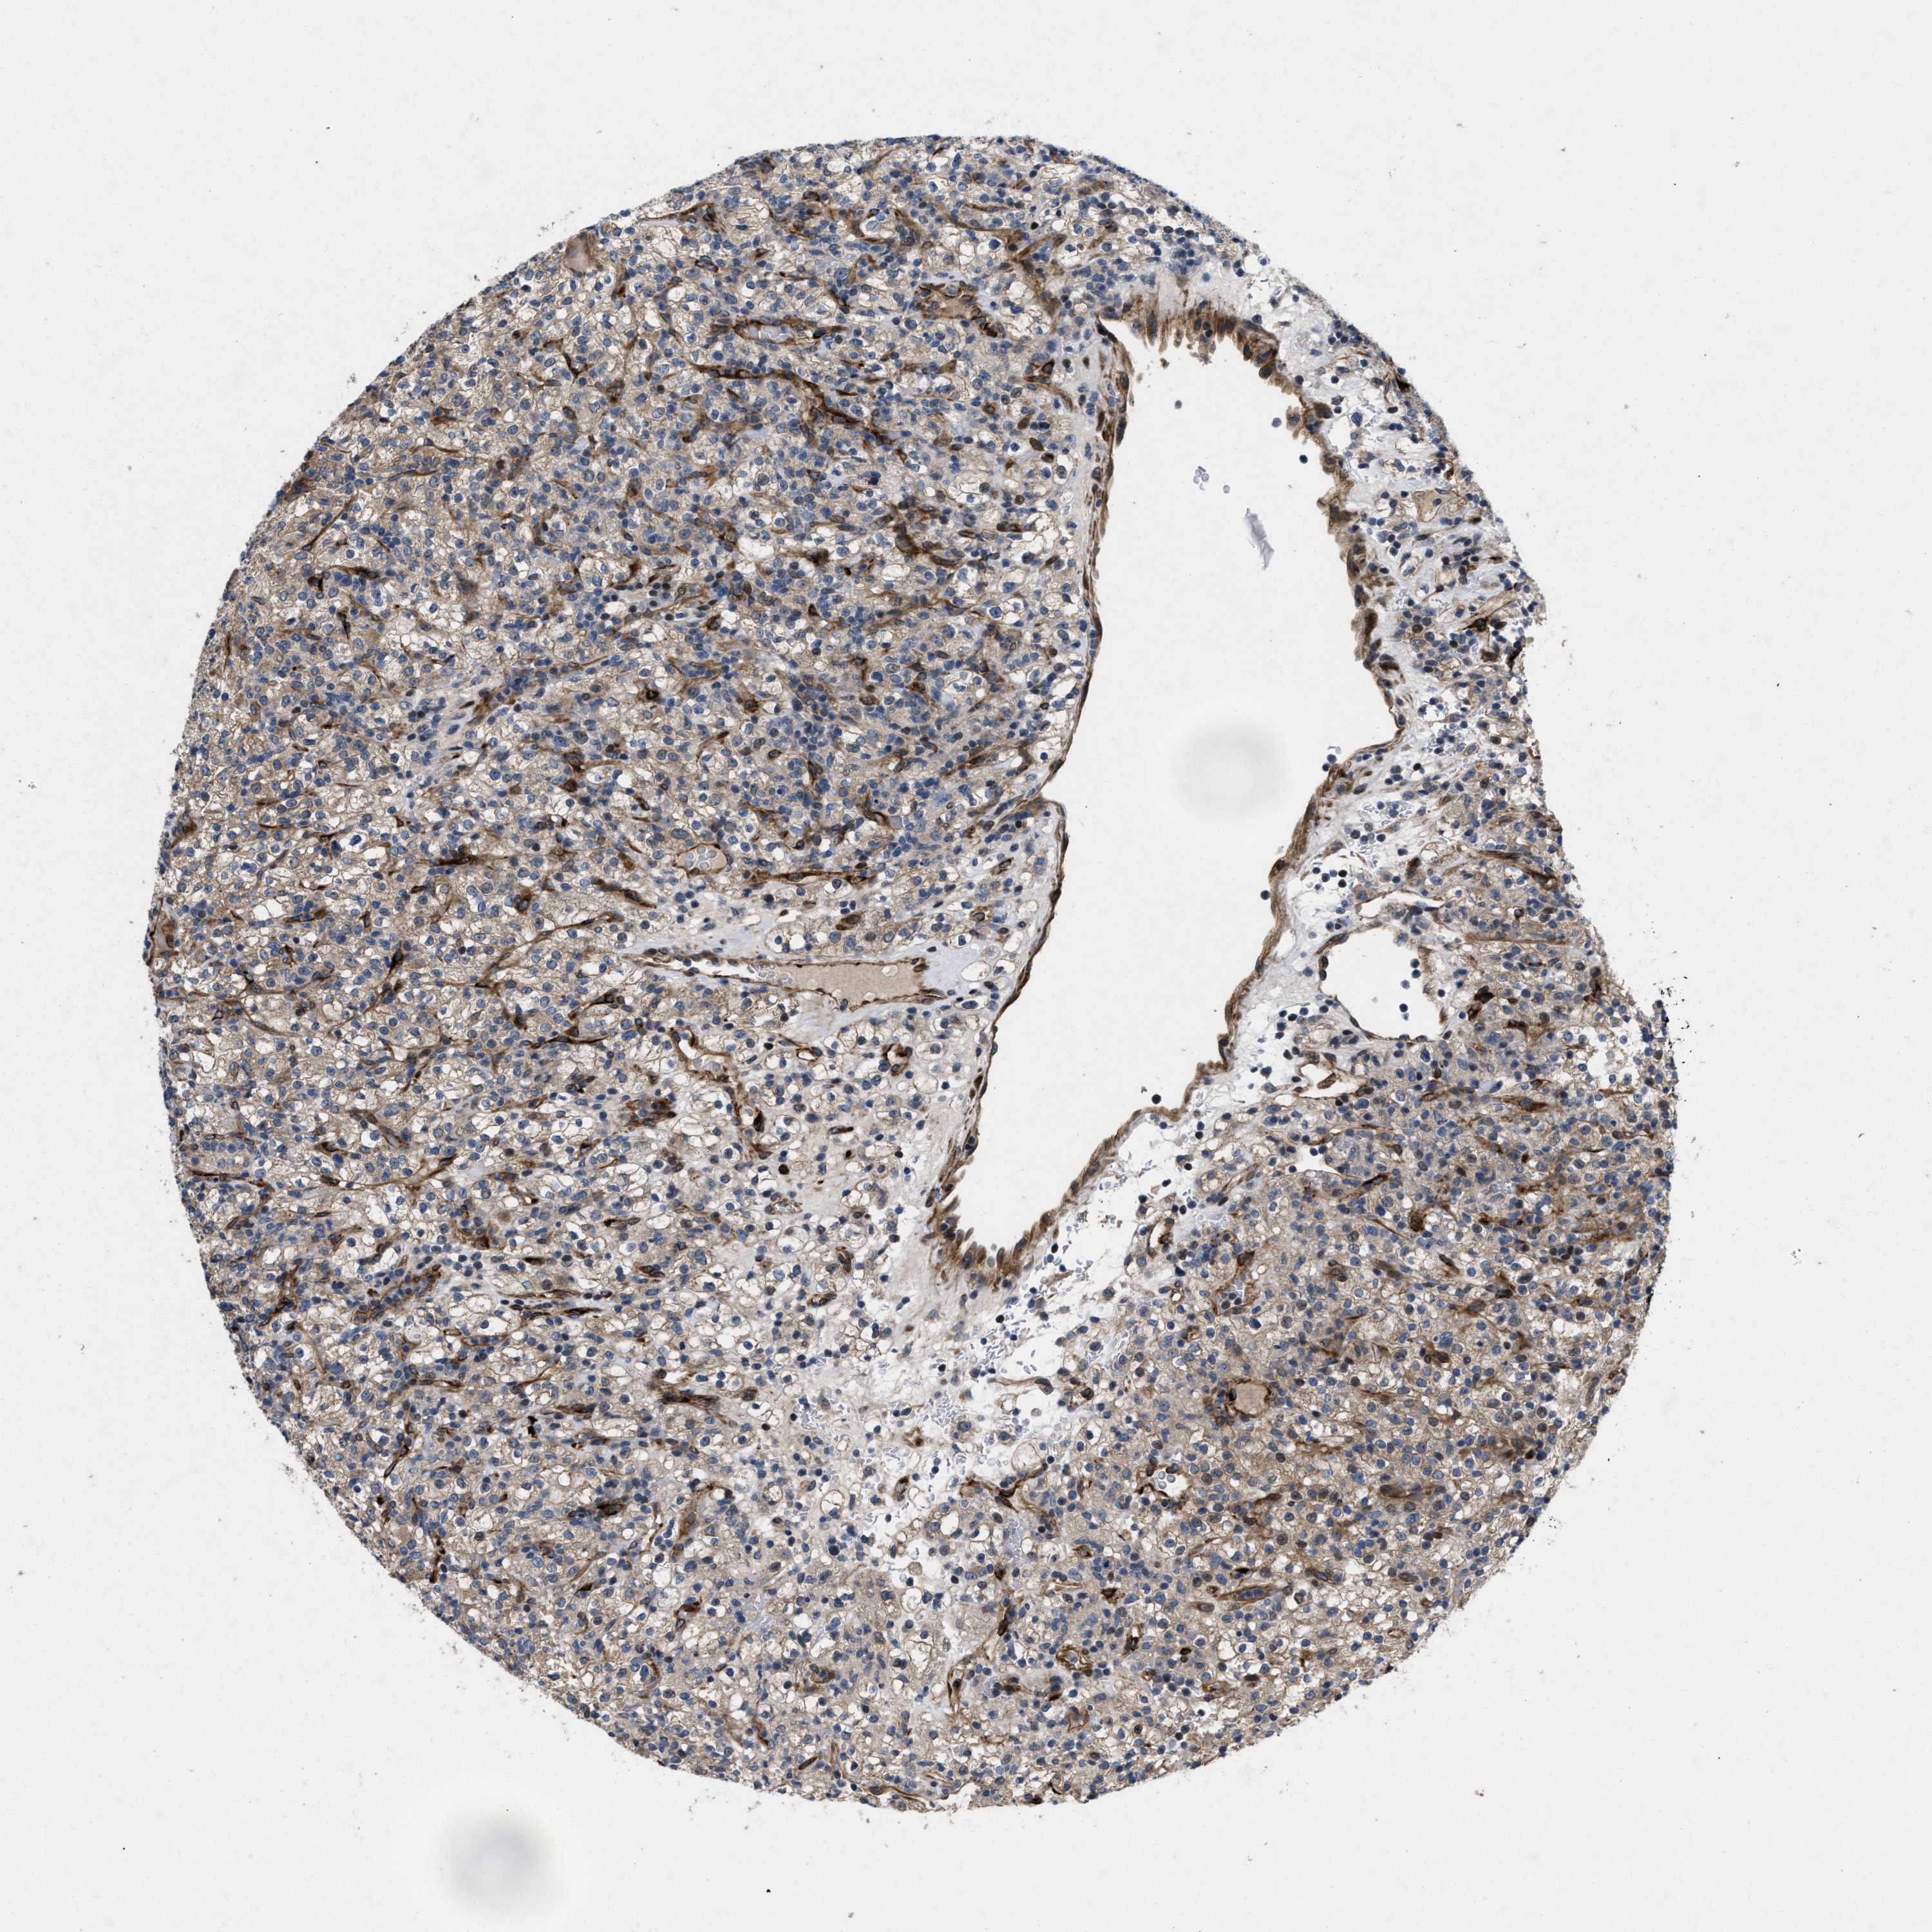

KIDNEY RENAL CLEAR CELL CARCINOMA (VALIDATION) - Interactive survival scatter ploti

The Survival Scatter plot shows the clinical status (i.e. dead or alive) for all individuals in the patient cohort, based on the same data that underlies the corresponding Kaplan-Meier plots. Patients that are alive at last time for follow-up are shown in blue and patients who have died during the study are shown in red.

The x-axis shows the expression levels (FPKM) of the investigated gene in the tumor tissue at the time of diagnosis. The y-axis shows the follow-up time after diagnosis (years). Both axes are complimented with kernel density curves demonstrating the data density over the axes. The top density plot shows the expression levels (FPKM) distribution among dead (red) and alive patients (blue). The right density plot shows the data density of the survived years of dead patients with high and low expression levels respectively, stratified using the cutoff indicated by the vertical dashed line through the Survival Scatter plot. This cutoff is automatically defined based on the FPKM cutoff that minimizes the p-score. The cutoff can be changed by dragging the vertical line or by entering a cutoff value in the square labeled "Current cut-off".

Under the Survival Scatter plot the p-score landscape (black curve; left axis) is shown together with dead median separation (red curve; right axis). Dead median separation is the difference in median mRNA expression between patients who have died with high and low expression, respectively. It is calculated as follows: median FPKM expression of dead patients with high expression - median FPKM expression of dead patients with low expression. This is intended to aid the user in visually exploring custom cutoffs and the associated p-scores and dead median separation.

Individual patient data is displayed and can be filtered by clicking on one or more of the category buttons on the top of the page. Categories describing expression level and patient information include: high, low, alive, dead, female, male and tumor stages. The scale of the x-axis can be toggled between linear and log-scale by clicking on the "x log" button. Mouse-over function shows TCGA ID, patient information and mRNA expression (FPKM) for each patient.

& Survival analysisi

Kaplan-Meier plots summarize results from analysis of correlation between mRNA expression level and patient survival. Patients were divided based on level of expression into one of the two groups "low" (under cut off) or "high" (over cut off). X-axis shows time for survival (years) and y-axis shows the probability of survival, where 1.0 corresponds to 100 percent.

HSPA12B is validated prognostic, high expression is favorable in Kidney Renal Clear Cell Carcinoma (validation)

: 3.53

Average pTPM 7.7

Number of samples 100